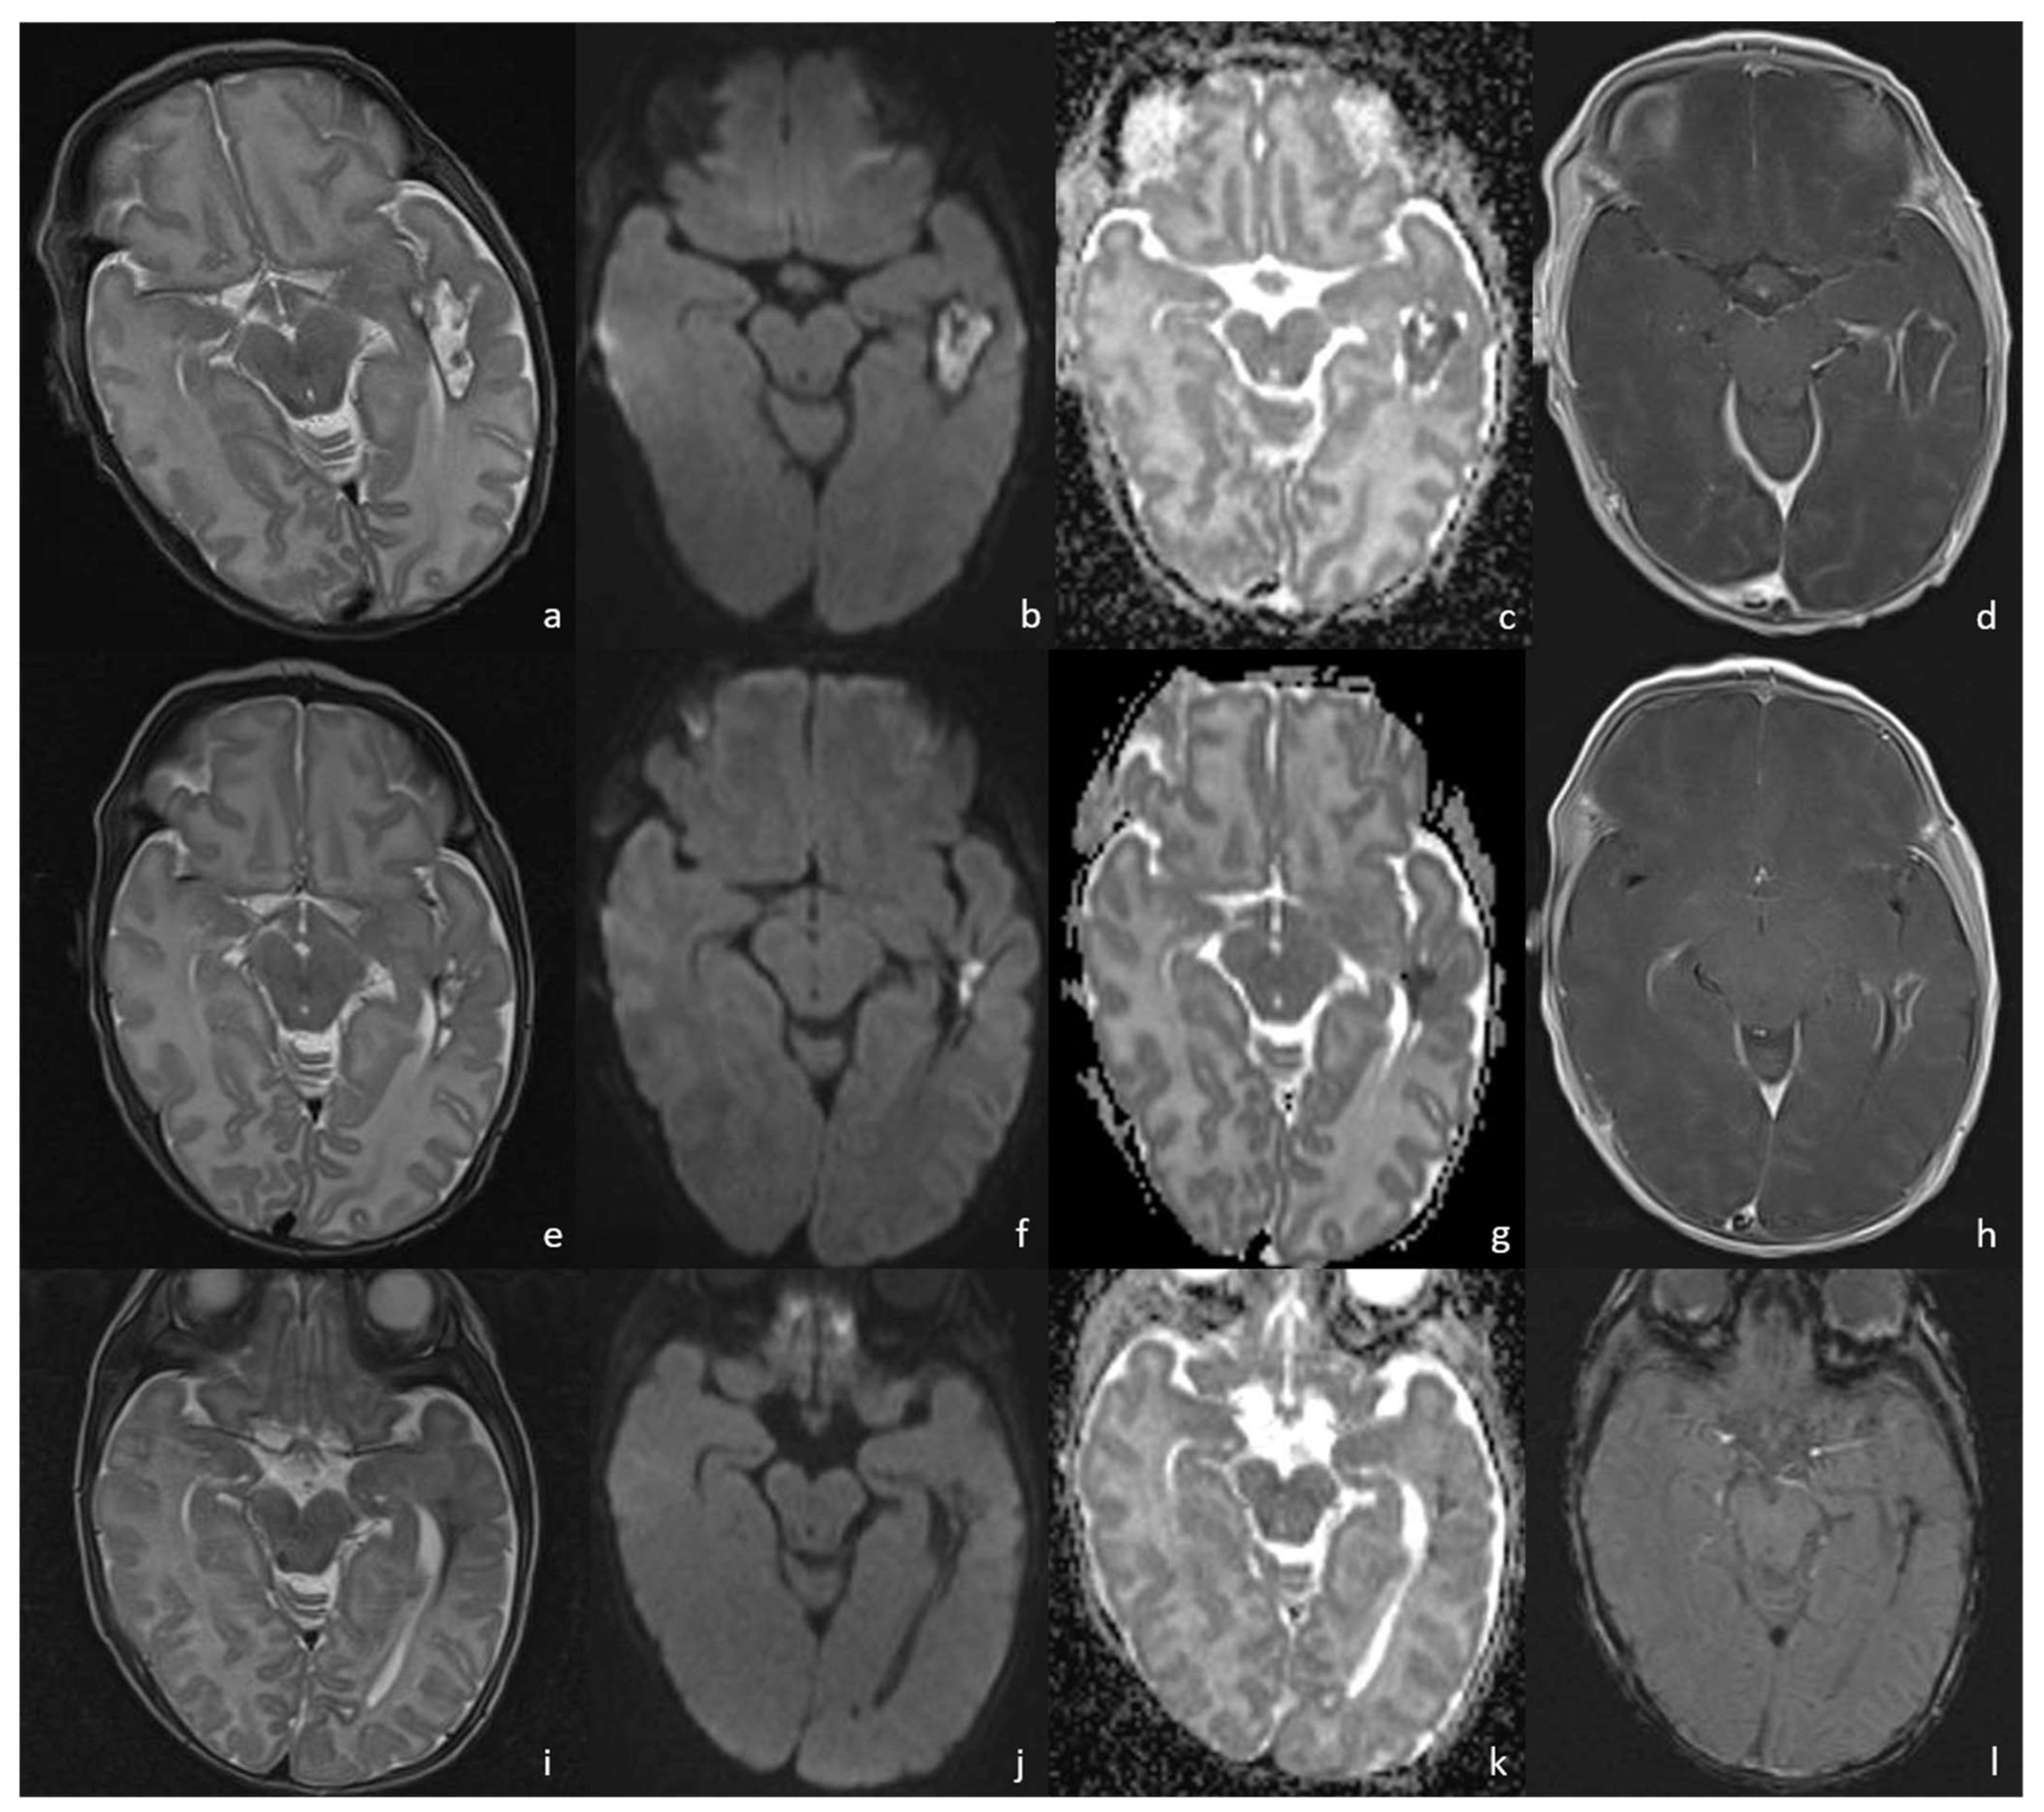

- Early cerebritis stage (3–5 days): Bacteria infiltrate the vessels causing vessel wall inflammation and vessel necrosis, which lead to blood barrier disruption and parenchymal invasion. The resulting cerebral infection, namely the early cerebritis, is limited to a focal portion of the brain, does not present a capsule, and presents a coexisting edema. In MRI, early cerebritis is seen as an inhomogeneous and ill-defined area of hyperintensity on T2WI and hypointensity on T1WI, surrounded by edema appearing hypointense on T1WI and hyperintense on T2WI. It presents a diffusion restriction on DWI/ADC in relation to cytotoxic edema and inflammatory hypercellularity. Hemorrhagic foci present as T1WI hyperintense areas within the lesion. After contrast administration, a patchy enhancement is observed, yet no capsule may be identified. On the US, early cerebritis appears as an ill-defined area of inhomogeneous echogenicity presenting increased vascularity on Transcranial Doppler, pairing CT findings, with an ill-defined area of inhomogeneous hypodensity with inhomogeneous and patchy enhancement.

- Late cerebritis (5–14 days): Cerebritis progressively evolves to show a necrotic core and an initial encapsulation. This stage flows into and partly overlaps with the early capsule stage since this last represents a progression with similar, yet more advanced features of the late cerebritis stage. In MRI, the late cerebritis results in a focal formation characterized by a necrotic core, appearing inhomogeneous on both T1 and T2WI, without a complete and regular contrast peripheral enhancement, yet with a defined diffusion restriction on DWI/ADC. On the US, the appearance is similar to the early cerebritis, yet the lesion appears more focal and the core starts becoming hypoechogenic, similar to CT showing a significantly hypodense core in the lesion with irregular and incomplete peripheral enhancement. Early capsule formation (14–30 days): The cerebritis is becoming an abscess since the capsule is evident, yet it is incomplete and thin and appears as a hyperintense rim on T1WI and a hypointense rim on T2WI with contrast enhancement on T1WI.

- Early capsule formation (2 weeks to 2 months): the lesion presents diffusion restriction on DWI/ADC, mainly in relation to hypercellularity. Sonographically, the lesion presents a well-defined hypoechoic core and an incomplete hyperechoic rim. CT shows a well-defined hypodense core and an incomplete peripheral enhancement.

- Late capsule formation (weeks to months): The parenchymal abscess presents a necrotic core, appearing hypointense on T1WI and hyperintense on T2WI with diffusion restriction on DWI/ADC. The capsule is inhomogeneously thick, appearing thicker towards the cortex and thinner towards the ventricles, appears isointense on T1WI and hypointense on T2WI, and presents an intense enhancement. On the US, the abscess presents a well-defined hypoechoic core and a complete hyperechoic rim, pairing CT that shows a well-defined hypodense core and a complete peripheral enhancement.